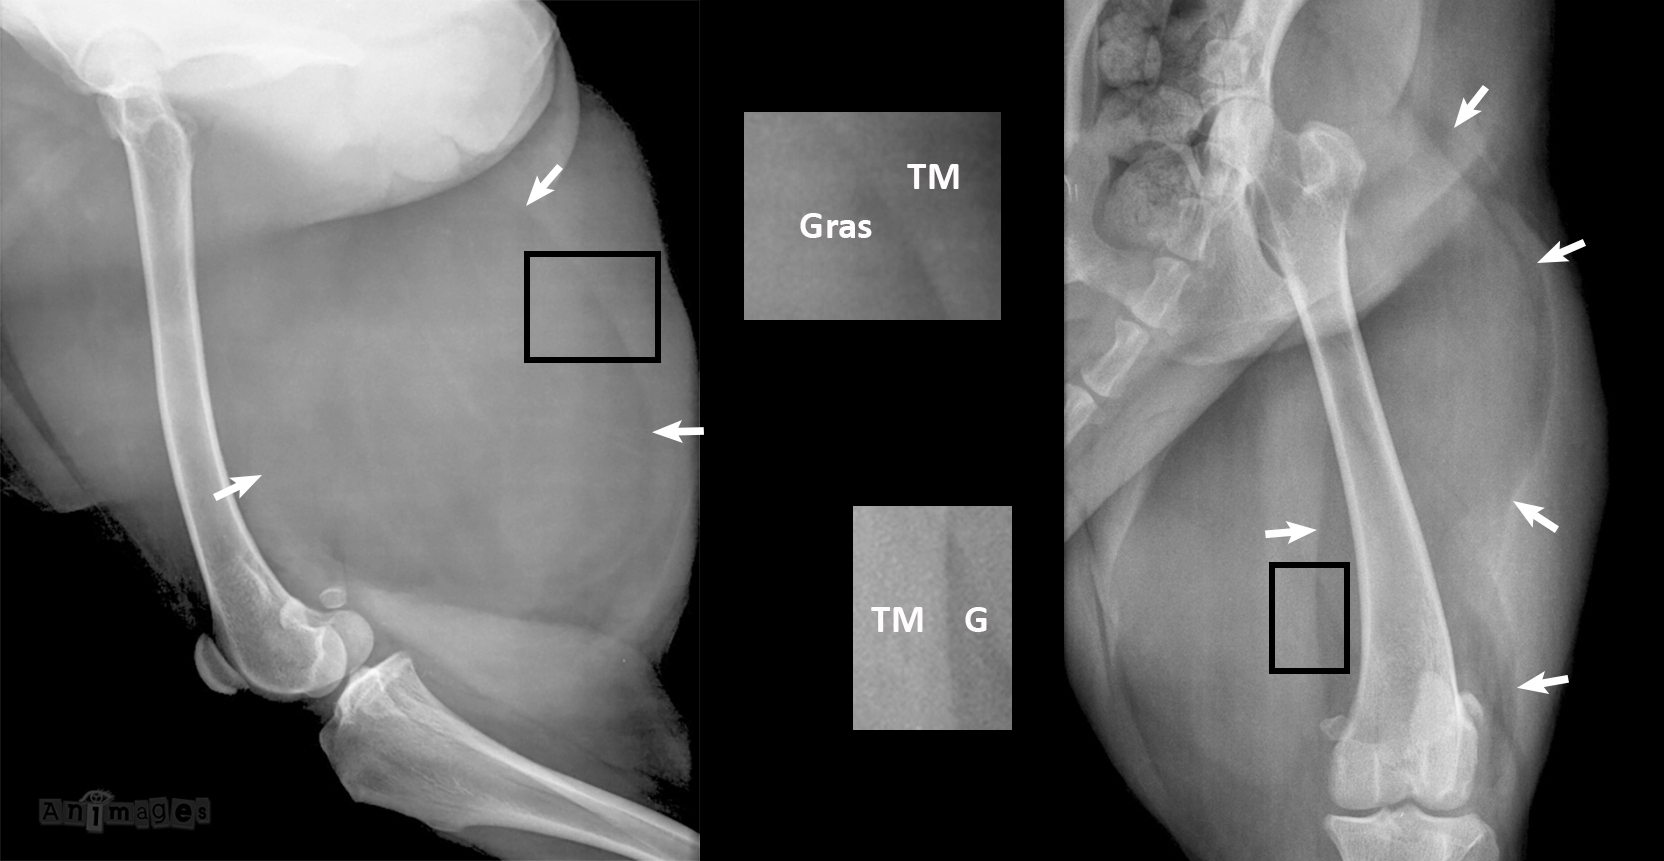

On examinant le sondage sur ce cas, on constate que les deux différentiels privilégiés étaient: lipome (42%) et sarcome des tissus mous de la cuisse (40%). Un ostéosarcome de la tête fémorale (11%), une déchirure musculaire (5%) ou un sarcome synovial (2%) étaient moins fréquemment suspectés. Une faible majorité a vu juste ! Il s’agissait bien d’un large lipome dont l’opacité graisseuse (G) se démarque de celle des tissus mous (TM), permettant de visualiser les contours (flèches) de la masse sur les deux projections. Un sarcome des tissus mous – même bien délimité – aurait été confondu aux muscles environnants dont l’opacité est similaire, à moins évidemment d’être minéralisé de façon extensive.